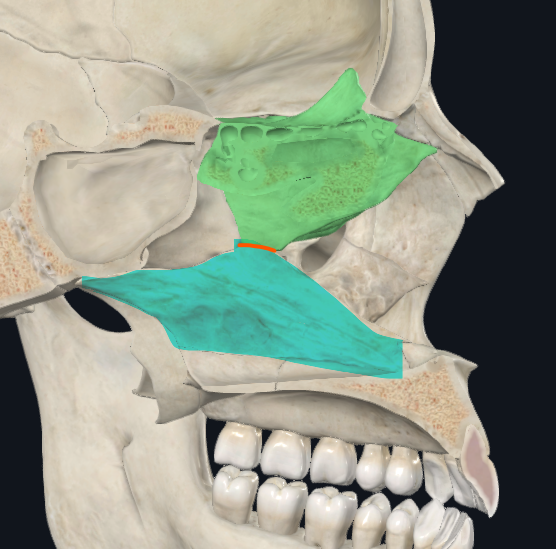

Unguis, Nasales

Huesos con los que articula anteriormente

Hueso frontal

Borde superior del etmoides

Maxilar superior, Palatino

Bordes inferiores del etmoides

Vómer

Borde posteroinferior del Etmoides

Hueso esfenoides

Cara posterior del Etmoides

Cornete nasal superior

Cornete nasal medio

Meato superior

Las celdas etmoidales POSTERIORES drenan a este meato

Meato medio

Las celdas etmoidales ANTERIORES, el seno frontal y el seno maxilar drenan a este meato